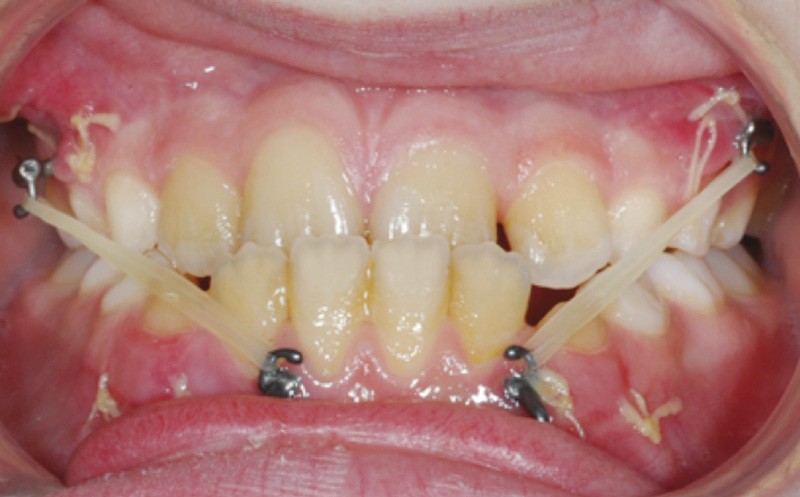

Dès l’évolution des canines mandibulaires, les plaques ont été fixées, et 3 semaines après, malgré une grande sensibilité au niveau du secteur I, la mécanique élastique de classe III a été commencée (fig. 2).